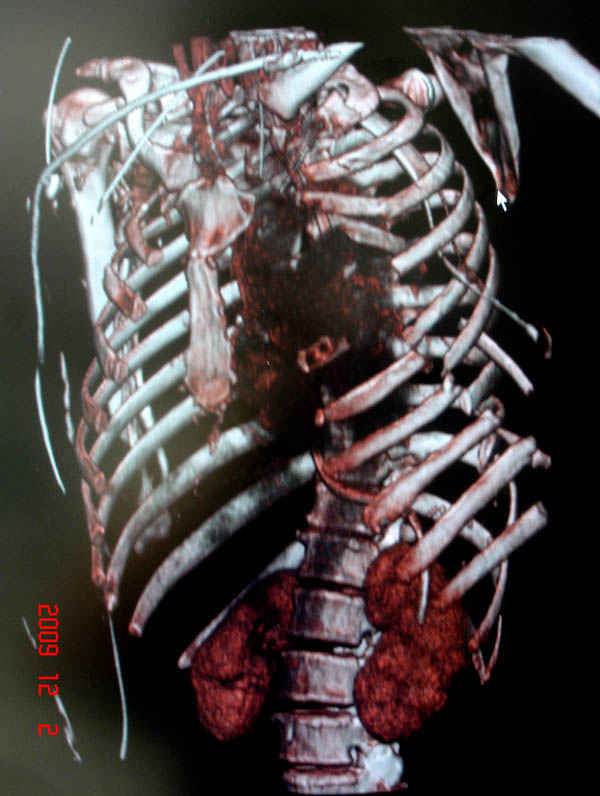

К нам поступила больная 56 лет после автоаварии в бессознательном состоянии, которая срочно заинтубирована в приемном отделении и сделаны необходимые исследования. Данные КТ и рентген показали перелом дистального бедра и Dissociation upper extremity - закрытый отрыв левой верхней конечности на уровне грудинно-ключичного сочленения и множественные переломы ребер.

На поверхности грудной клетки из-за полного разрыва грудной мышцы под кожей заметно биение сердца и след от ремня безопасности. Грудная клетка расширена из-за смещения верхней конечности вверх и латерально. Признаков васкулярного повреждения нет, и из-за отсутствия сознания не смогли определить наличия повреждения нервов.

На седьмые сутки нами совместно с торакальным хирургом сделана операция по фиксации грудинно-ключичного сочленения и переломов ребер.

После кожного разреза обнаружили полный разрыв грудной мышцы и повреждение перикард от уровня второго до восьмого ребер. Хирург находился с нами и после нашей работы зафиксировал повреждение перикарда и разрыв грудной мышцы.

Не все переломы ребра фиксированы, и поэтому хотели услышать комментарии тех, у кого имеется опыт.

В основном переломы ребер мы тоже не фиксируем, но учитывая, что в данной презентации, кроме разрыва грудинно-ключичного сочленения, дополнительно имелись множественные переломы ребер, некоторые сегментарные. После такой травмы трудно восстановить функцию западающей грудной клетки, и поэтому после дисскуссии с торакальным хирургом мы коллективно приняли решение зафиксировать переломы ребер тоже.

Отмеченный Александром случай из России заинтриговал меня давно и как раз выдался случай..., тем более новый имплант от Synthesа в 1.5 мм отвечал всем требованиям остеосинтеза ребер.